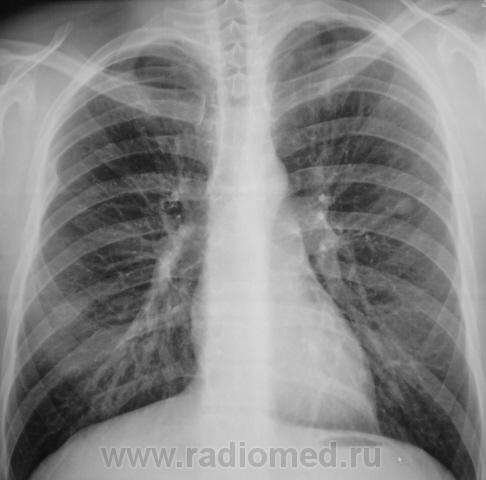

Пол пациента: Мужской пол Тип патологии: Другое Область исследования: Грудная клетка и верхние дыхательные пути Методы исследования: Rg Туберкулома? https://radiomed.ru/sites/default/files/styles/case_slider_image/public/user/12/2.pb240005a.jpg?itok=xfKB85vZ ID:9364 Thu, 25/11/2010 - 01:21 #1 Катенёв Валенти... Offline Last seen: 7 years 3 weeks ago Joined: 22.03.2008 - 22:15 Posts: 54876 Продолжение. [[wysiwyg_imageupload:690:]][[wysiwyg_imageupload:691:]][[wysiwyg_imageupload:692:]][[wysiwyg_imageupload:693:]] Thu, 25/11/2010 - 05:24 #2 Helios Offline Last seen: 7 months 3 weeks ago Joined: 06.08.2010 - 15:16 Posts: 4417 А здесь?Приложения: Thu, 25/11/2010 - 14:34 #3 lupan Offline Last seen: 6 years 10 months ago Joined: 07.01.2010 - 17:17 Posts: 1406 Helios wrote: А здесь? Туберкулома-то имеется. Но не она здесь самая "страшная". Великое преймущество врача заключается в том, что он не обязан следовать собственным советам. ( А. Кристи) Thu, 25/11/2010 - 14:46 #4 Катенёв Валенти... Offline Last seen: 7 years 3 weeks ago Joined: 22.03.2008 - 22:15 Posts: 54876 Наша "туберкулома", конечно, требует д/диагностики с периферическим раком лёгкого. Thu, 25/11/2010 - 21:06 #5 Катенёв Валенти... Offline Last seen: 7 years 3 weeks ago Joined: 22.03.2008 - 22:15 Posts: 54876 Пациент прооперирован в ОПТД, диагноз подтвержден. Снимки ниже.Приложения: Thu, 25/11/2010 - 21:13 #6 Катенёв Валенти... Offline Last seen: 7 years 3 weeks ago Joined: 22.03.2008 - 22:15 Posts: 54876 Фрагменты снимков и томограмма.Приложения:

Туберкулома-то имеется. Но не она здесь самая "страшная".

Наша "туберкулома", конечно, требует д/диагностики с периферическим раком лёгкого.

Пациент прооперирован в ОПТД, диагноз подтвержден. Снимки ниже.